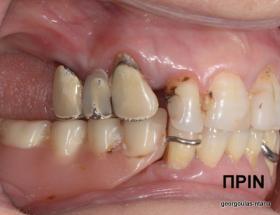

Η ασθενής αυτή είχε παλιές ακίνητες αποκαταστάσεις (γέφυρες) στην άνω γνάθο  κ μια κινητή προσθετική αποκατάσταση (μερική οδοντοστοιχία-"μασελάκι") στην κάτω γνάθο. Ήταν δυσαρεστημένη τόσο με την εμφάνιση όσο και με τη λειτουργία των δοντιών της καθώς παραπονιόταν ότι  είχαν εντονη κινητικότητα ενώ και οι προσθετικές τους εργασιές δεν ήταν σταθερές. Η πρόγνωση των δοντιών κρίθηκε φτωχή με αποτέλεσμα να μην είναι δυνατή η συμμετοχή τους σε μια νεα προσθετική αποκατάσταση με μακροχρόνια διάρκεια. Η ασθενής επιθυμούσε οι νέες αποκαταστάσεις να είναι σταθερές και ακίνητες.  Για το λόγο αυτό αποφασίστηκε η ολική αποκατάσταση της άνω κ κάτω γνάθου με ακίνητες επιεμφυτευματικές εργασίες. Στην αριστερή πλευρά της άνω γνάθου, λόγω μη επαρκούς οστού για την τοποθέτηση εμφυτευμάτων προηγήθηκε επέμβαση ανοιχτής  ανύψωσης ιγμορείου άντρου με τη χρήση πιεζοχειρουργικού μηχανήματος ώστε να δημιουργηθεί το κατάλληλο οστικό υπόστρωμα. Ακολούθησε σε επόμενο χειρουργείο η εξαγωγή των υπάρχοντων δοντιών κ η άμεση τοποθέτηση εμφυτεύματων (άμεση εμφύτευση) κ δύο μέρες μετά η τοποθέτηση προσωρινής εργασίας επί των εμφυτευμάτων (άμεση φόρτιση) με αποτέλεσμα η ασθενής να μη μείνει καθόλου χωρίς δόντια κ να είναι καλυμένη αισθητικά όσο καιρό διήρκησε η εργασία